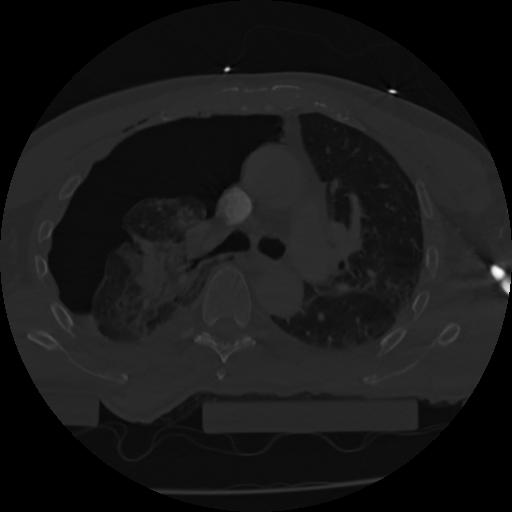

22 ANGIO,CE,Vol,0.5,ANGIO,,